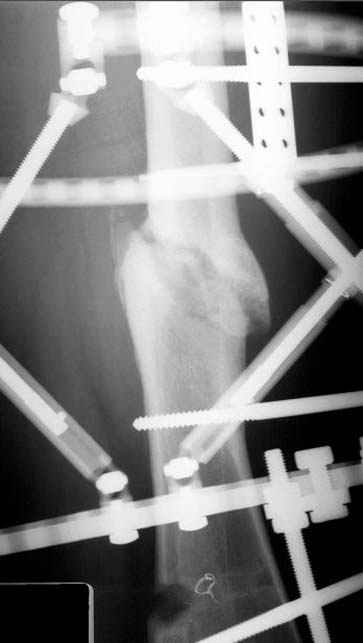

Несколько снимков из моей коллекции, чтобы разьяснить, почему мы до сих пор делаем различные варианты остеотомии.

На рисунке N1 предоперационный план лечения ложного сустава шейки бедра- линия ложного сустава, угол и направление введения импланта, клиновидная остеотомия в градусах и миллиметрах, второй снимок после коррекции, расчет, на сколько удлиняется конечность и размеры импланта;

N3 рисунок окончательный снимок, после операции моя рентгенограмма должен выглядеть примерно как эта картина. На N4 снимке клин перед удалением; N5 послеоперации 3 нед.; N6 окончательная рентгенограмма.

Djoldas Kuldjanov 23 Ноябрь 2004, 18:21

пластическая модель; и коррекция бедра аппаратом Илизарова.